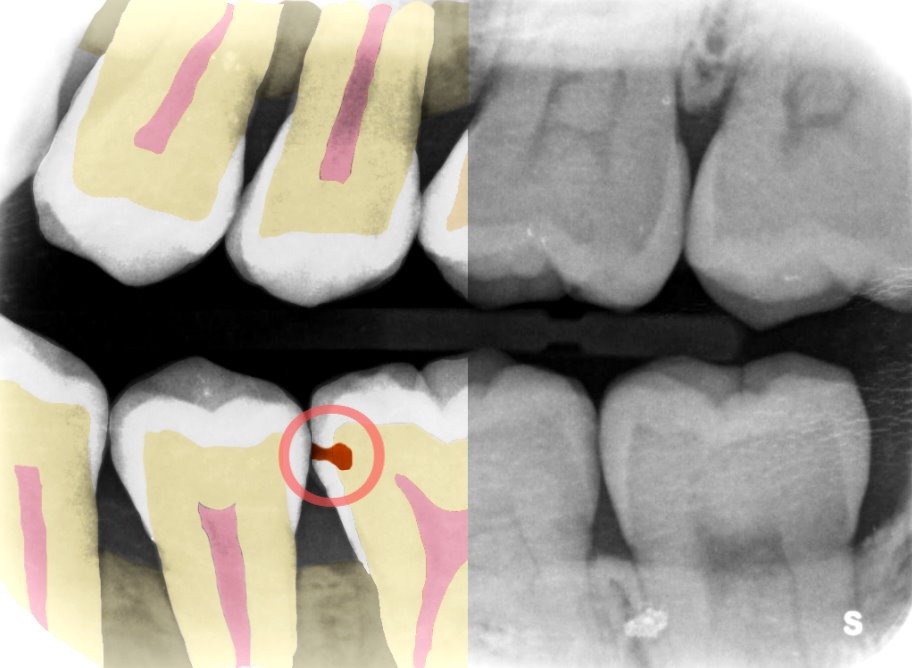

Providing the perspective of a more experienced dentist, Adra’s intent is to make every dentist “a super dentist,” Fesharaki told TechCrunch. Its software detects cavities and other dental problems on dental X-rays faster and 25% more accurately, so that clinics can use that time to better serve patients and increase revenue.

“We are coming from the eye of an experienced dentist to help illustrate the problems by turning the X-rays into images to better understand what to look for,” he added. “Ultimately, the dentist has the final say, but we bring the experience element to help them compare and give them suggestions.”

By quickly pointing out the problem and the extent of it, dentists can decide in what way they want to treat it — for example, do a filling, a fluoride treatment or wait.